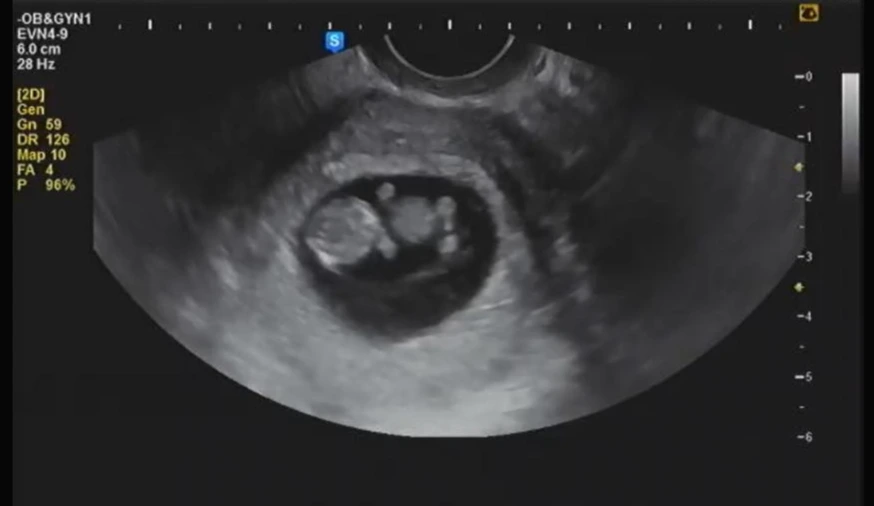

임신 9주 차, 마치 곰인형처럼 보이는 "봉주"

나는 아내가 건네준 파우치를 받아들고 조심스럽게 열어보았다. 그 안에는 수첩과 사진 그리고 작은 약통이 하나 있었다. 수첩에는 아내의 이름이 적혀 있었고, 사진에는 둥글둥글한 형체의 얼굴, 몸통, 팔과 다리가 마치 곰인형처럼 보이는 태아가 있었다. 그리고 작은 약통은 엽산이었다.

"나 임신했어, 벌써 9주 차래"

그렇게 나는 아빠가 되었다. 결혼기념일 선물로 아내가 건네준 것은 우리 부부의 2세가 생겼다는 확인된 징표였다. 초음파 사진이 아니고서는 그 존재를 느끼기가 쉽지는 않았지만 우리의 아이는 아내의 뱃속에서 자리 잡고, 건강하게 성장하고 있었다.